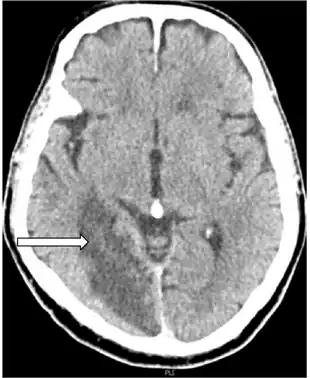

| Anton syndrome because of Bilateral Ischemic Occipital Lobe Strokes-image indicates nonhemorrhagic cerebral infarction arrow | |